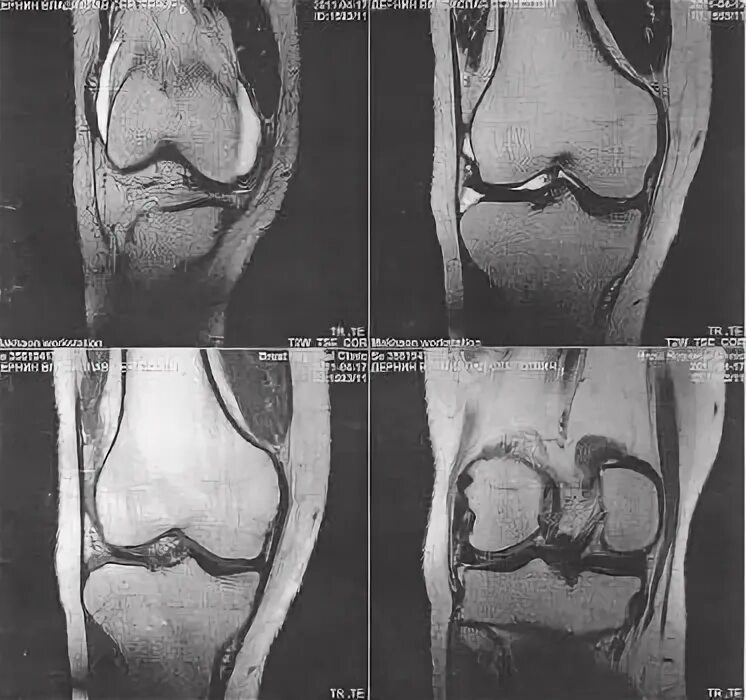

Повреждение мениска мрт